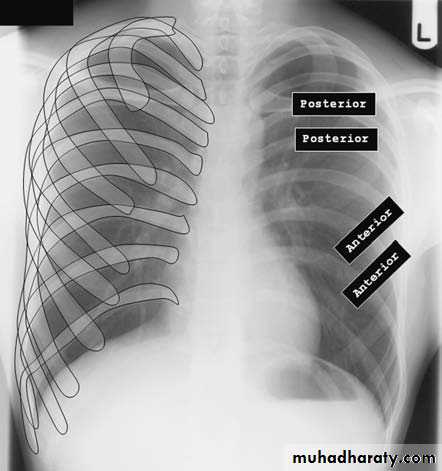

3) PA view( patient facing the cassette )

PA(postero-anterior )

Anterior ends of ribs & clavicles directed downwardAP(infants & bed ridden patients )

anterior ends of ribs & clavicles directed upwardPA VERSUS AP PROJECTION:

Avoid the magnification of the heart.Protect the radio-sensitive organs, lens of the eye, thyroid gland, breast tissue in females and gonads.

Displace the scapula and clavicles away from the lung shadow.

5)Full inspiration

The diaphragm should be below theanterior end of 6th rib & posterior end of 10th rib .